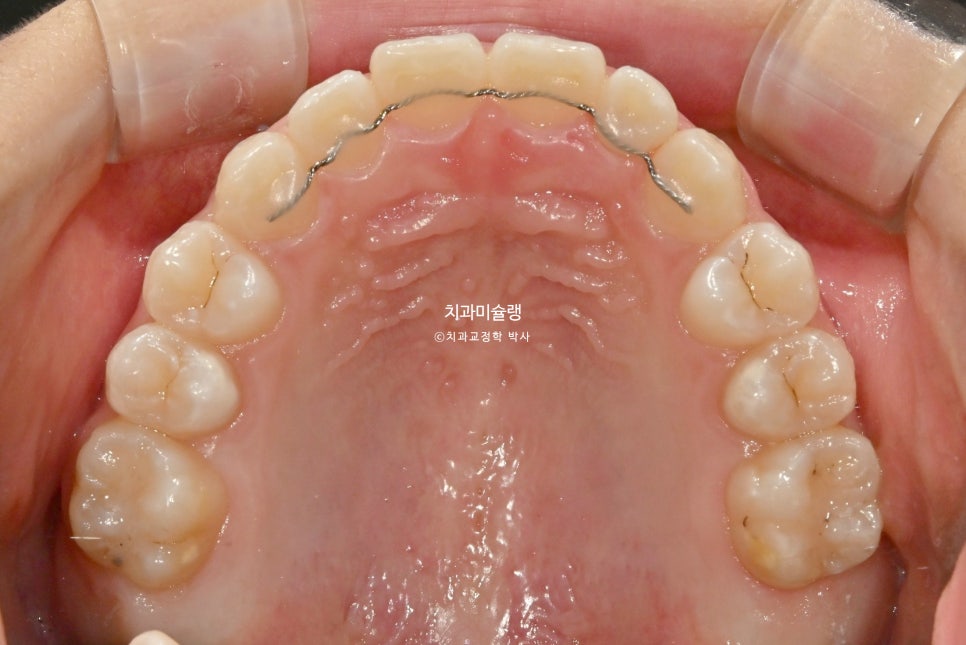

치료 완료 시 결과

중심선은 잘 맞으며 절단교합으로 인항 개방교합은 해소되었습니다.

어금니 교합관계는 1급을 달성.

3급 교합관계를 1급으로 만들기 위해 치료기간 내내 3급 고무줄을 사용했습니다.

결과가 성인교정치료 결과에 준한만큼 유지장치도 성인과 동일하게 들어갑니다.